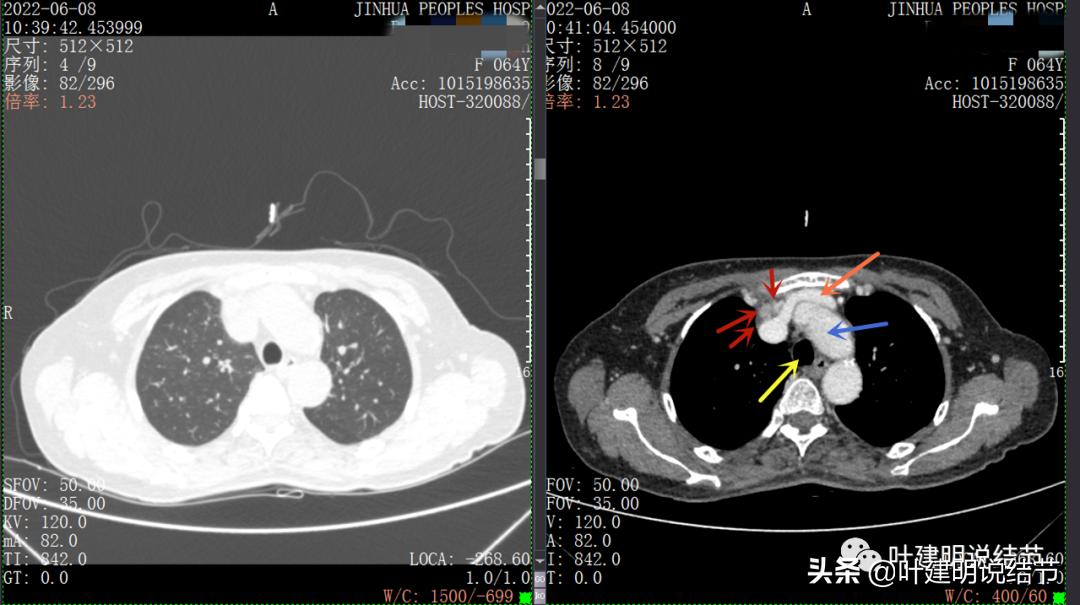

以下图片左侧是肺窗,右侧是纵隔窗。红色箭头示病灶,桔色箭头示无名静脉,黄色箭头示支气管,砖色箭头示上腔静脉,蓝色箭头示主动脉,紫色箭头示肺动脉。

病灶纵隔胸膜侧非常光滑,说明来源于纵隔

粉色箭头示淋巴结可能